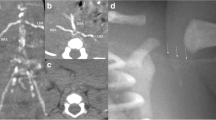

Vascular calcifications are the earliest and most dramatic feature of GACI (Fig. 1a–d). In a comprehensive literature review by Chong et al. involving 161 patients, 48% presented in utero or shortly after birth, termed “early onset,” and 52% presented after birth (median 3 months), termed “late onset” [16]. These groups had both distinct and overlapping clinical features. In early-onset GACI, patients most commonly presented with signs of fetal circulatory compromise, including hydrops fetalis, polyhydramnios, and fetal distress. Patients with late-onset disease were often asymptomatic at birth, but developed progressive signs of cardiovascular disease, including respiratory distress, cyanosis, and feeding difficulties.

Clinical images of vascular calcifications in patients with GACI. a Coronal views of a computed tomography scan shows diffuse calcification involving the descending aorta (red arrow) and multiple branching arteries (yellow asterisks). b Prenatal ultrasound demonstrates calcification and severe narrowing in the distal aorta (red arrow). c Axial views of a computed tomography scan show a calcified and severely narrowed descending aorta (red arrow). d Medium-sized pancreatic artery showing calcification (red arrows) along the internal elastic lamina (hematoxylin and eosin stain)

A wide variety of arteries may be affected by calcifications. In the Chong et al. review, autopsies revealed that early-onset disease most commonly involved the hepatic (81%), aortic (80%), and pulmonary arteries (67%), while in late-onset disease, the coronary (88%), renal (55%), and pulmonary arteries (49%) were most affected [16]. However, these results reflect autopsies performed at numerous centers over an extensive period, and standardized studies with well-defined disease criterion are needed to characterize arterial involvement.